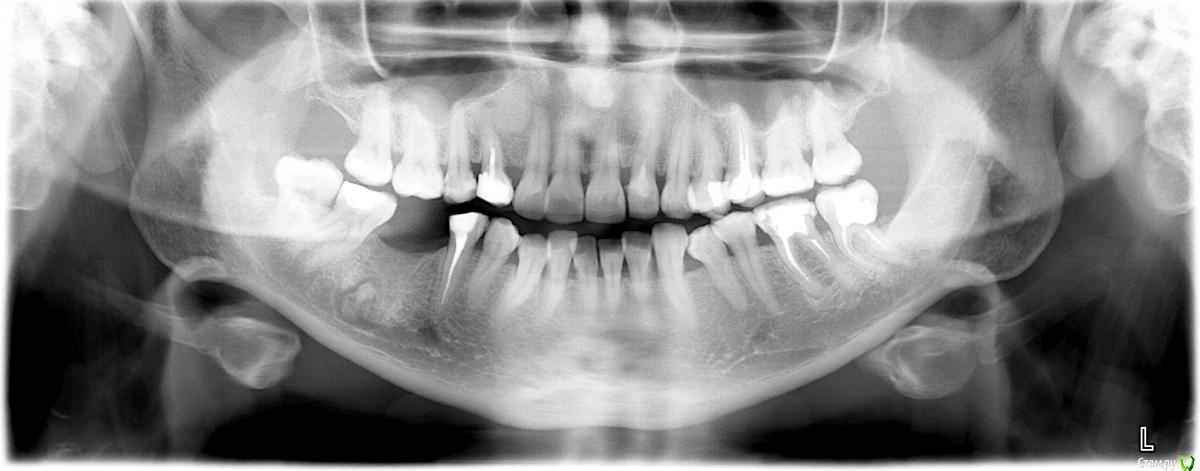

L.E.S.I.K. Опубликовано 29 мая, 2017 Поделиться Опубликовано 29 мая, 2017 Коллеги, нужна помощь. Обратилась пациентка с желанием поставить имплант в область 46 зуба. На орто и КТ вот такая картина. Не могу понять это остаток корня, зона остеосклероза...? Лучше удалять или не лезть и поставить имлант рядом? Ссылка на комментарий

Dman Опубликовано 29 мая, 2017 Поделиться Опубликовано 29 мая, 2017 Были похожие случаи, но там были застарелые удаления, остатки без разрежений вокруг. Оба раза ставили рядом. Вся соль в том, если полезете доставать, то так распашете, что ни о какой одномоментной установке речи идти не будет, + потом может понадобиться НКР. Ну и канал рядом... Ссылка на комментарий

dok1 Опубликовано 29 мая, 2017 Поделиться Опубликовано 29 мая, 2017 Убирать этот корень обязательно. Ибо в оболочке он. Неанкилозированный. Ссылка на комментарий